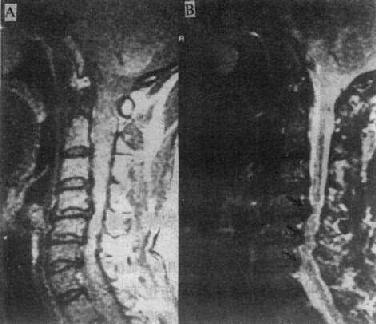

MRI可清楚地显示椎管狭窄,包括椎体与脊椎小关节的增生、韧带肥厚和椎间盘脱出等。如果椎间盘脱出发生在多个平面,且相对的黄韧带肥厚,则在与椎间隙水平相对应的硬膜囊前后缘受压,在矢状面T2WI上,硬膜囊呈串珠状表现(图2-2-4)。

质子密度像 T2WI

图2-2-4p; 颈椎关节病颈4~6段的蛛网膜下腔及脊髓于椎间盘水平均受压变细,呈典型的糖葫芦状